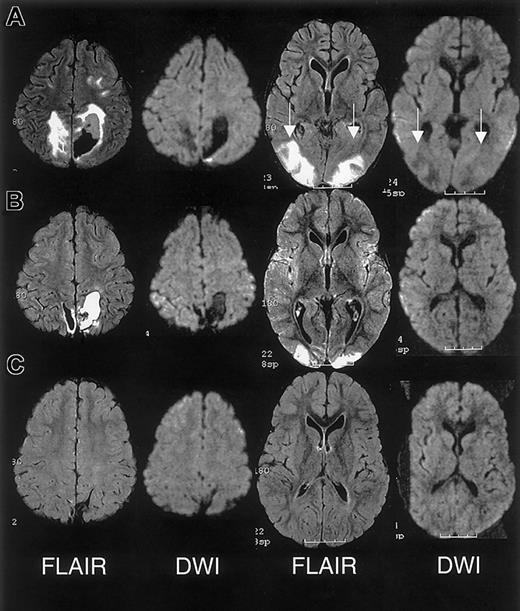

RPLS is difficult to distinguish from acute cerebral infarcts clinically and radiographically. The distinction is important because cerebral infarction implies irreversible damage and warrants blood transfusion therapy for an indefinite period. Conversely, RPLS is potentially reversible but may require judicious hypertensive management. In this case series, 2 patients were originally diagnosed as having cerebral infarcts according to the clinical reading of the MRI, one of whom was subsequently determined to have RPLS and the other with cerebral hemorrhage. Appropriate MRI techniques and interpretation play a key role in differentiating RPLS from cerebral infarct (Figure 4). Both RPLS and cerebral infarct present with T2-weighted hyperintensities. DWIs typically show hyperintense signal in cerebral infarcts, whereas DWIs in RPLS are ambiguous because of T2 shine-through effects.8 14 Producing images of the diffusion coefficient eliminates this ambiguity.

Characterization of T2-weighted hyperintensities on MRI of the brain distinguishing cerebral infarct from reversible posterior leukoencephalopathy syndrome (RPLS).

DWI indicates diffusion weighted image; DC, diffusion coefficient.